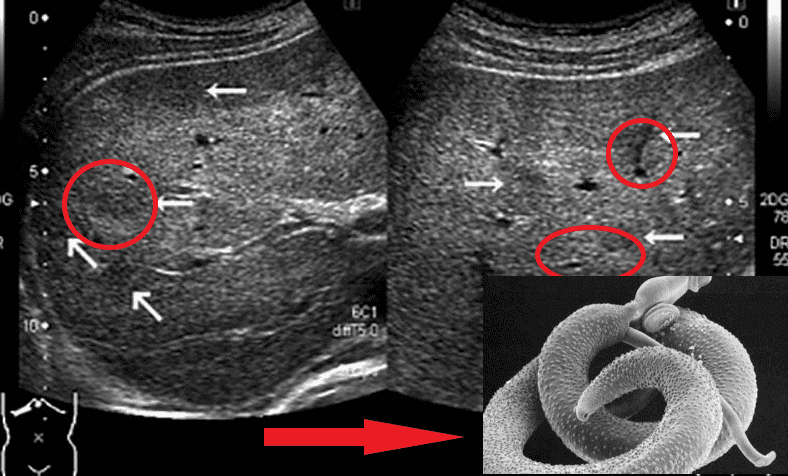

Мільйонні колонії паразитів заполоняють увесь організм і проникають з потоком крові у серце, легені, нирки, печінку й навіть мозок!

Мозок, уражений паразитами